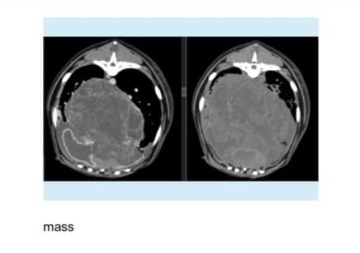

Nikdy by mě nenapadlo, že tu teď budu sedět a psát tuhle žádost o pomoc. Jinak úplně zdravá a vitální Mija najednou potřebuje pomoc, na kterou tentokrát já sama už nestačím. Před týdnem při vyšetření obyčejného kašle, přišel doktor na to, že má Mijuška v plicích tekutinu, která musela být v narkóze odsána a následným vyšetřením se zjistilo, že příčinou je nádor v hrudníku.

Vzhledem k jeho velikosti je nutné tento stav, co nejdříve vyřešit, jelikož z nádoru vytéká do hrudníku tekutina a musí se každé tři dny znovu odsávat. Tento akutní stav si žádal vyšetření CT a další.

Bohužel už na tato vyšetření a zákroky padla většina úspor a tak žádám o pomoc, jelikož doporučená operace na odstranění je předběžně vyčíslena na 120.000 Kč + pooperační péče. Tato léčba nám byla navrhnuta onkologem na základě zhodnocení celkového, jinak skvělého stavu Mijušky a mladého věku - 7 let.